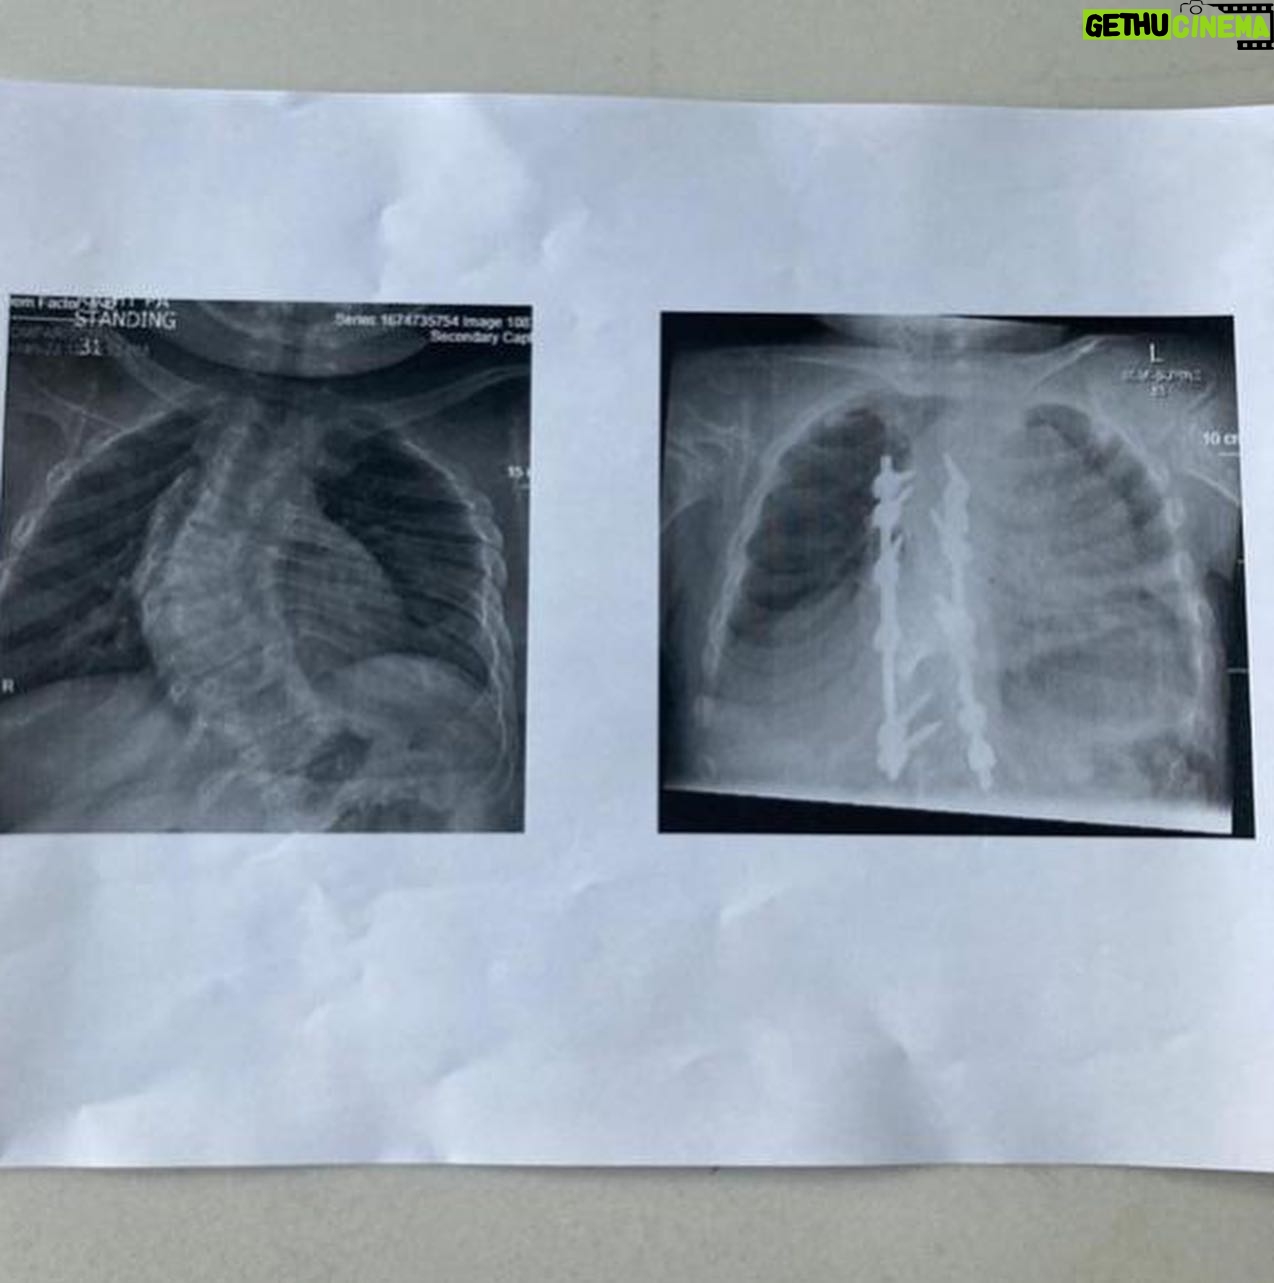

14.2K Likes – Lenny Rush Instagram

Caption : Today marks one year since my spinal fusion surgery. I cannot believe how fast time has gone, and to look at the pictures and see how I am doing now, is amazing! It was definitely a hard time, not just for me, but also my family. But seeing the X-rays and the shape of my back (and the therapy dogs that came to visit 🐶) really helped get me get through it. I am now doing better than ever! A massive thank you to @greatormondst : you’ve changed my life for the best! (The second picture shows my X-rays. The one on the left is before the surgery, and the one on the right is after 🩻). #recovery #spinalfusionsurgery #scoliosisLikes : 14189

14.2K Likes – Lenny Rush Instagram

Caption : Today marks one year since my spinal fusion surgery. I cannot believe how fast time has gone, and to look at the pictures and see how I am doing now, is amazing! It was definitely a hard time, not just for me, but also my family. But seeing the X-rays and the shape of my back (and the therapy dogs that came to visit 🐶) really helped get me get through it. I am now doing better than ever! A massive thank you to @greatormondst : you’ve changed my life for the best! (The second picture shows my X-rays. The one on the left is before the surgery, and the one on the right is after 🩻). #recovery #spinalfusionsurgery #scoliosisLikes : 14189

14.2K Likes – Lenny Rush Instagram

Caption : Today marks one year since my spinal fusion surgery. I cannot believe how fast time has gone, and to look at the pictures and see how I am doing now, is amazing! It was definitely a hard time, not just for me, but also my family. But seeing the X-rays and the shape of my back (and the therapy dogs that came to visit 🐶) really helped get me get through it. I am now doing better than ever! A massive thank you to @greatormondst : you’ve changed my life for the best! (The second picture shows my X-rays. The one on the left is before the surgery, and the one on the right is after 🩻). #recovery #spinalfusionsurgery #scoliosisLikes : 14189

14.2K Likes – Lenny Rush Instagram

Caption : Today marks one year since my spinal fusion surgery. I cannot believe how fast time has gone, and to look at the pictures and see how I am doing now, is amazing! It was definitely a hard time, not just for me, but also my family. But seeing the X-rays and the shape of my back (and the therapy dogs that came to visit 🐶) really helped get me get through it. I am now doing better than ever! A massive thank you to @greatormondst : you’ve changed my life for the best! (The second picture shows my X-rays. The one on the left is before the surgery, and the one on the right is after 🩻). #recovery #spinalfusionsurgery #scoliosisLikes : 14189

14.2K Likes – Lenny Rush Instagram

Caption : Today marks one year since my spinal fusion surgery. I cannot believe how fast time has gone, and to look at the pictures and see how I am doing now, is amazing! It was definitely a hard time, not just for me, but also my family. But seeing the X-rays and the shape of my back (and the therapy dogs that came to visit 🐶) really helped get me get through it. I am now doing better than ever! A massive thank you to @greatormondst : you’ve changed my life for the best! (The second picture shows my X-rays. The one on the left is before the surgery, and the one on the right is after 🩻). #recovery #spinalfusionsurgery #scoliosisLikes : 14189